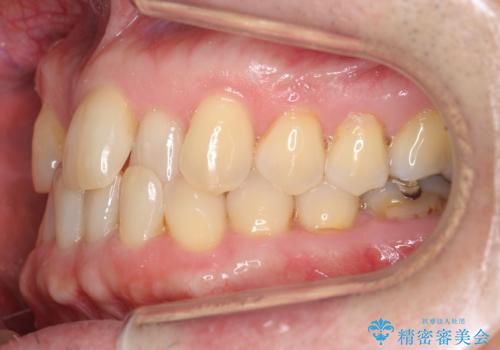

- 受け口を主訴に来院。

他院での矯正相談は、5年以上かかると言われ、やんわりお断りされたとのことでした。

ずっと矯正はしたかったがあきらめていて、50代で退職を機に新しいことを初めて、歯並びも諦めずに治したいとのことでした。顎の手術は避け、歯の移動だけでの治療をご希望されていました。

ある程度時間はかかることは説明させていただき、治療開始しました。

右上の八重歯は、右上の奥歯を矯正用ミニスクリューを用いて遠心移動を行い解消しました。